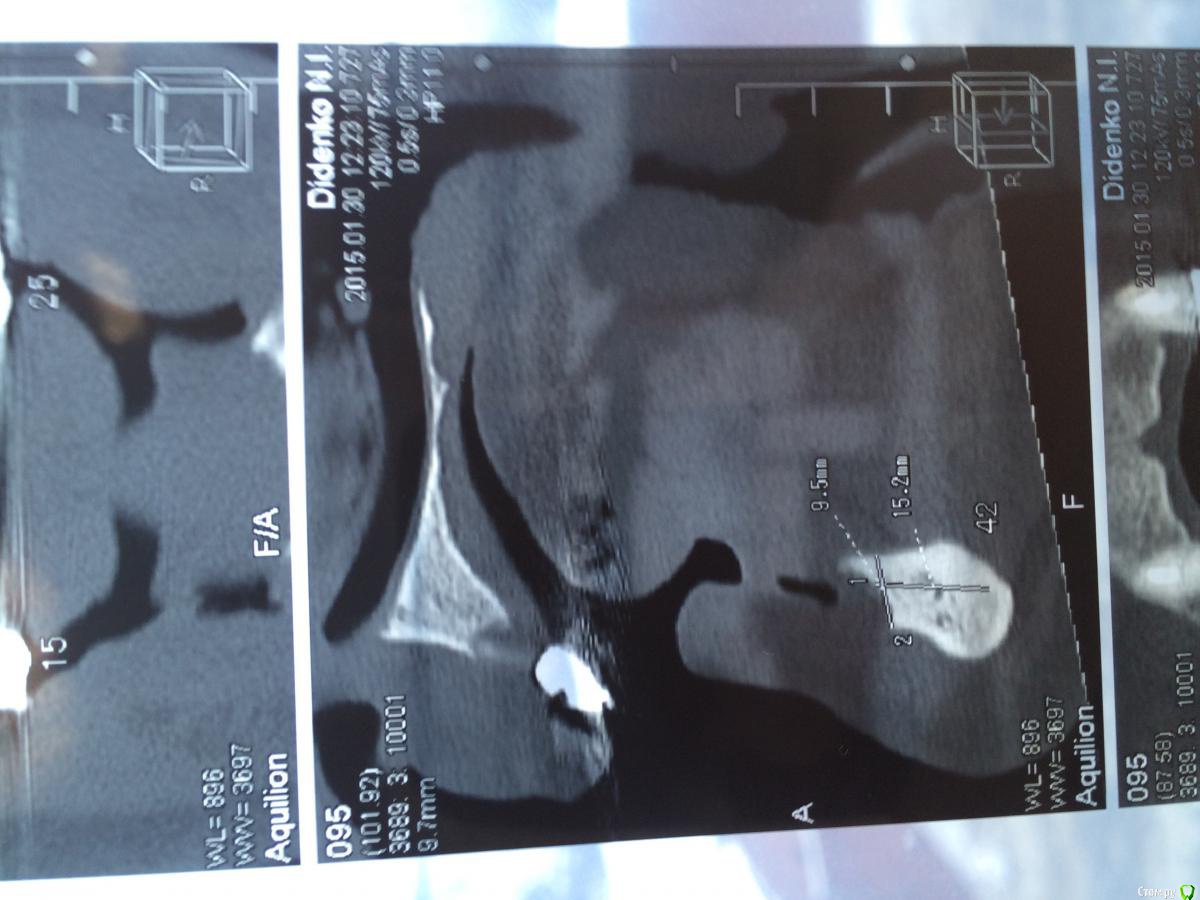

urseva19.05.10 Опубликовано 31 января, 2015 Поделиться Опубликовано 31 января, 2015 Коллеги, в каких позициях на ваш взгляд целесообразнее поставить имплантаты желательно без НКР ( пациент ограничен во времени) что бы в последствии протезироваться съемным протезом на локаторах? На верх не смотрите там все ясно Спасибо! Ссылка на комментарий

Alejandro Опубликовано 31 января, 2015 Поделиться Опубликовано 31 января, 2015 В области 36,46 толщина альвеоляра какая? Ссылка на комментарий

urseva19.05.10 Опубликовано 31 января, 2015 Автор Поделиться Опубликовано 31 января, 2015 10,5 и 9,2 соответственно Ссылка на комментарий

syrovovec Опубликовано 31 января, 2015 Поделиться Опубликовано 31 января, 2015 Ставьте в межментальное 2 или 4, как вам больше нравитсяPs фотки очень неудобно смотреть, срезы замеры не информативные 1 Ссылка на комментарий

Alejandro Опубликовано 31 января, 2015 Поделиться Опубликовано 31 января, 2015 Я бы поставил два межментально в области клыков, и два в области шестёрок тогда. Можно не сильно параллелить - на локаторах это прощается. Ссылка на комментарий

kriokov Опубликовано 31 января, 2015 Поделиться Опубликовано 31 января, 2015 1. выравнивайте гребень2. Позиции 34 , 32, 42, 44, если болты позволяют их субкрестально поставить , то притопите, и ушиться бы двурядно, Ссылка на комментарий

urseva19.05.10 Опубликовано 1 февраля, 2015 Автор Поделиться Опубликовано 1 февраля, 2015 1. выравнивайте гребень2. Позиции 34 , 32, 42, 44, если болты позволяют их субкрестально поставить , то притопите, и ушиться бы двурядно, 1. Всё-таки считаете без НКР не обойтись?2. С 32,42 понятно, а если в области 36,46 установить не будет ли лучше фиксация протеза, да и условия вроде позволяют. Как думаете? Ссылка на комментарий